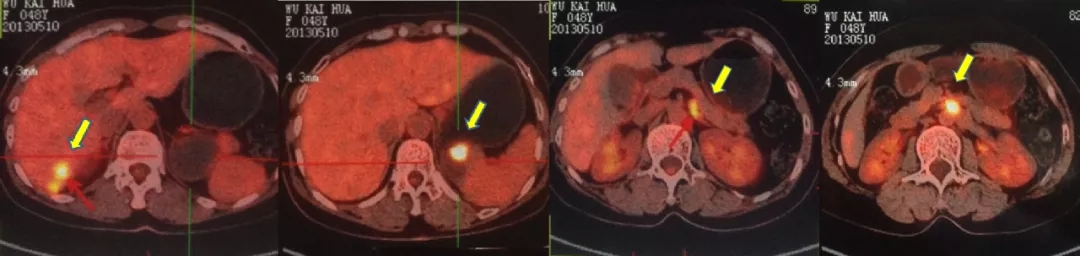

2021.4.23复查CA125上升至70.2U/ml。2021.4.24 CT:肝肾隐窝病灶增大,考虑复发。患者退出BGB-290临床试验。

2021.5.8 PET-CT:肝肾隐窝转移灶。2021.5.12复查CA125水平为95.5U/ml。

PET-CT检查结果